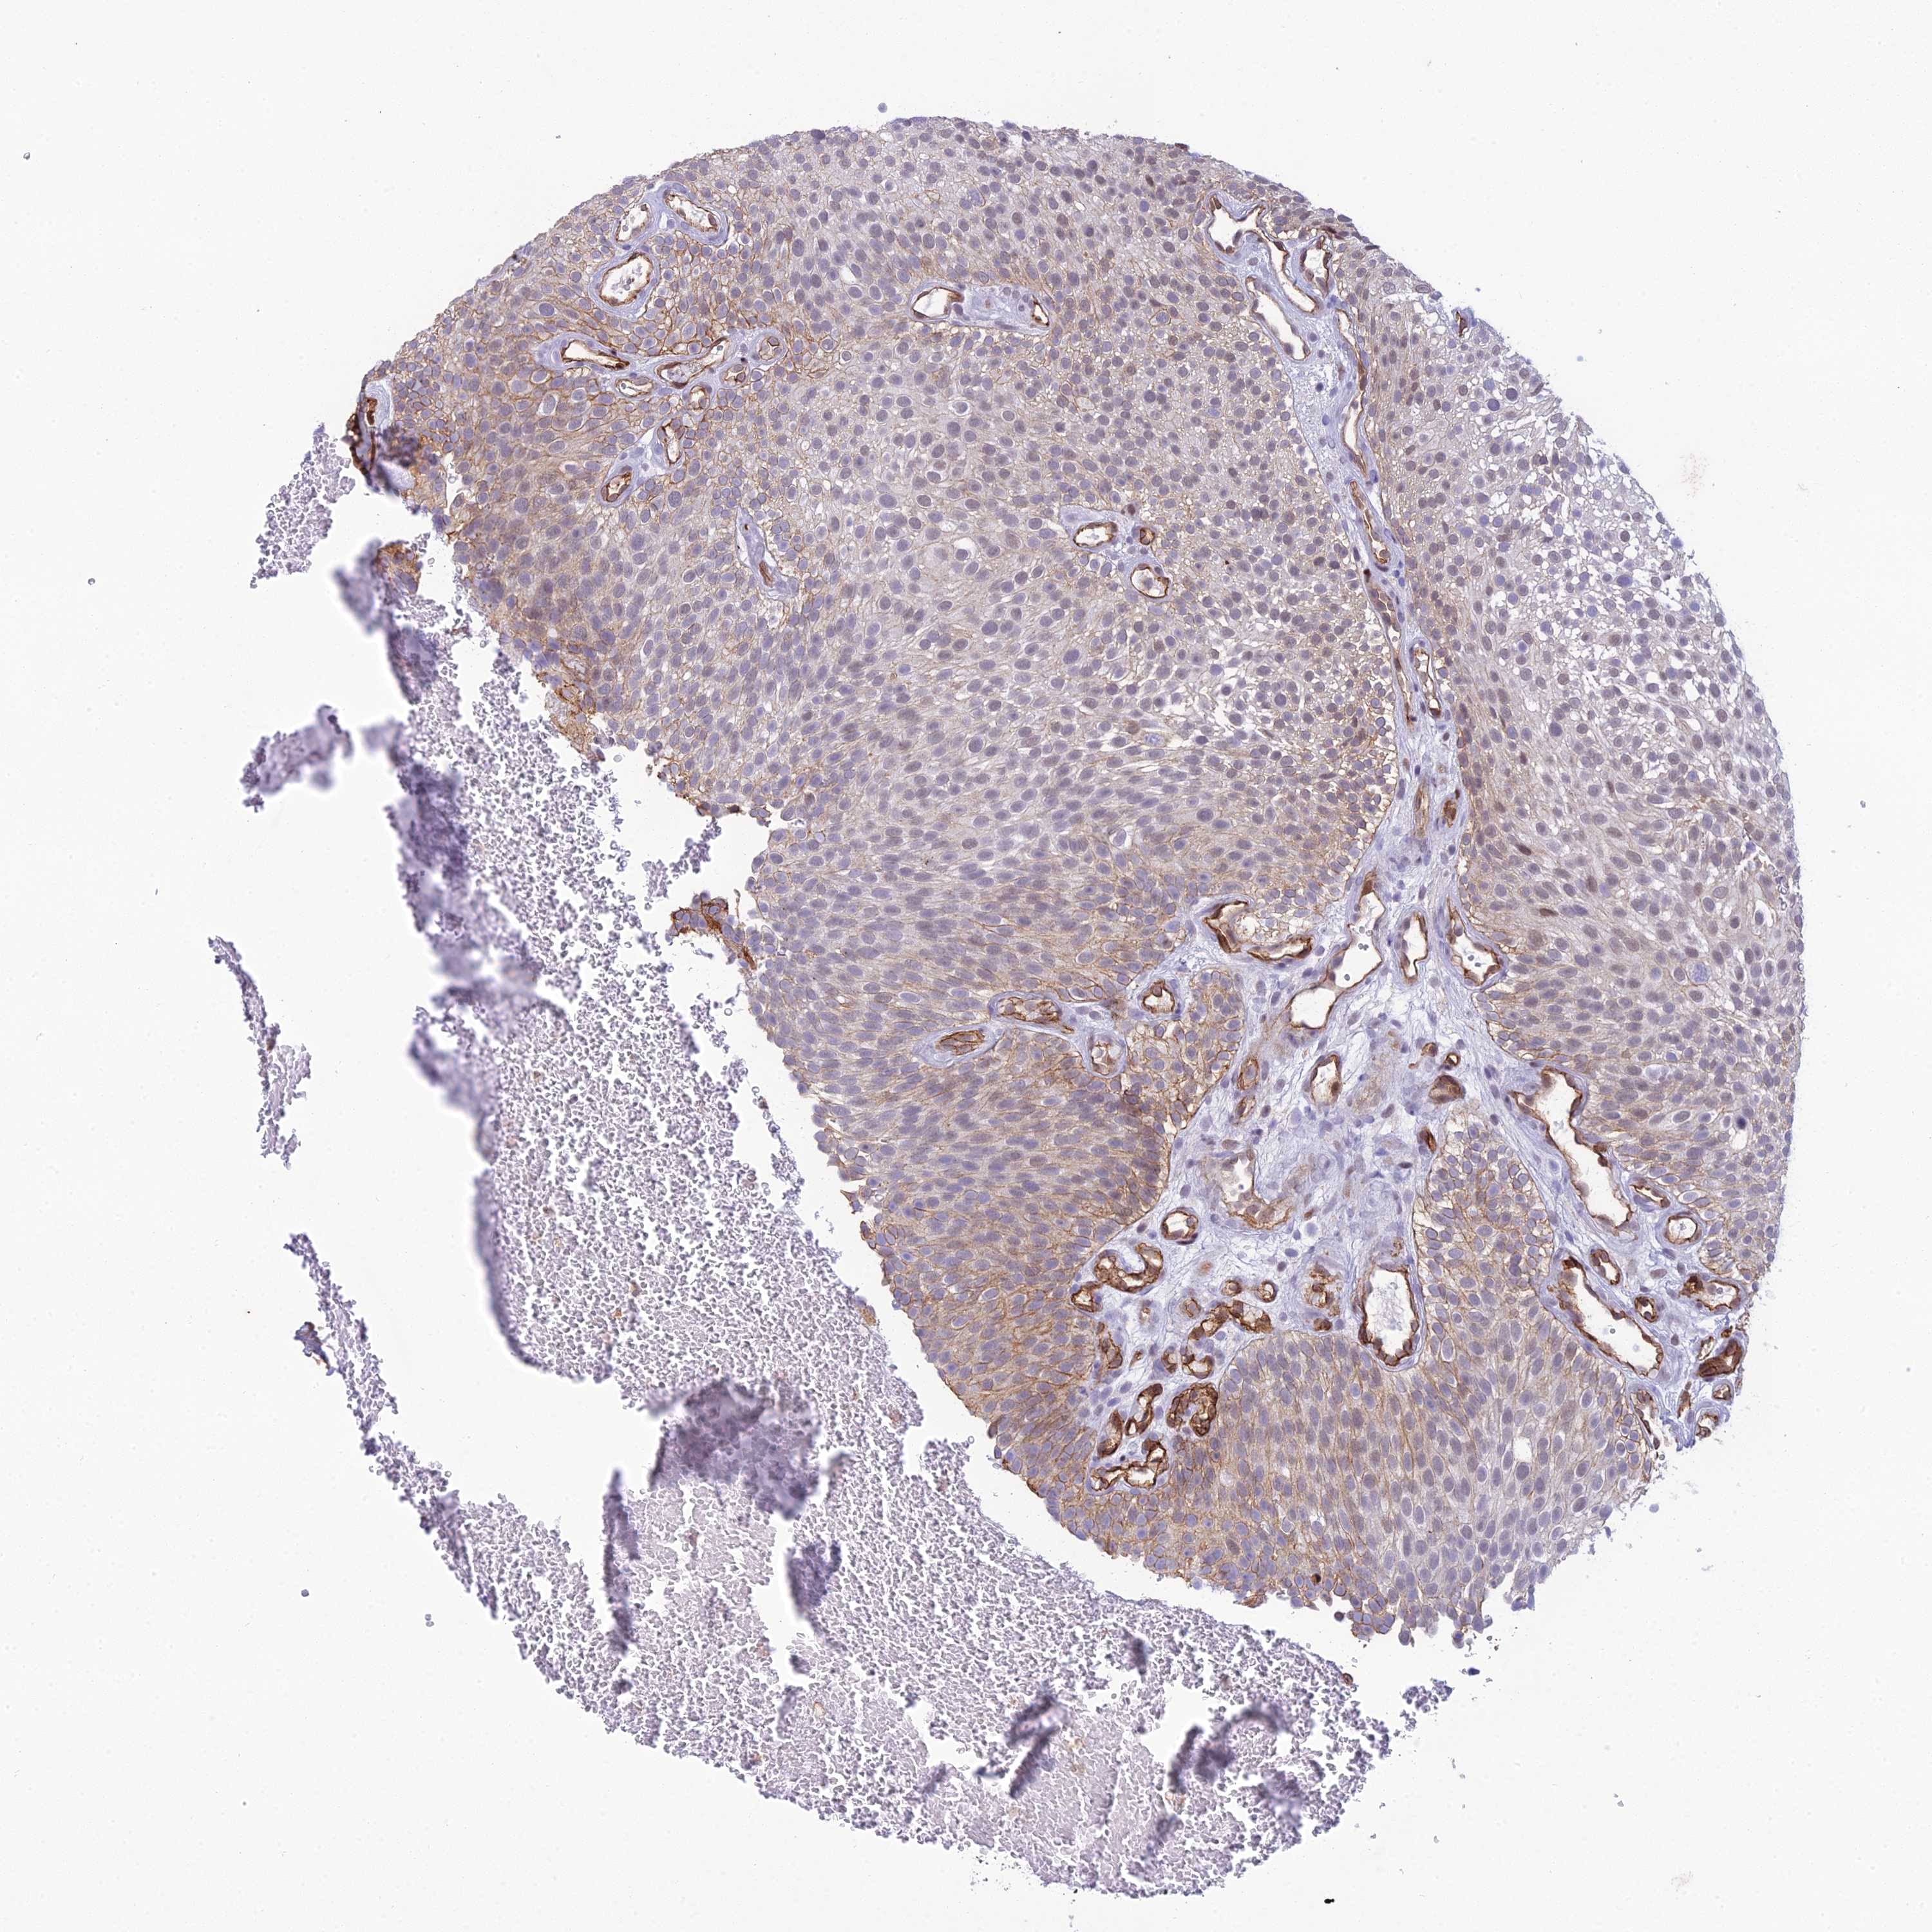

UROTHELIAL CANCER - Protein expressioni

A mouse-over function shows sample information and annotation data. Click on an image to view it in a full screen mode. Samples can be filtered based on level of antibody staining by selecting one or several of the following categories: high, medium, low and not detected. The assay and annotation is described here.

Note that samples used for immunohistochemistry by the Human Protein Atlas do not correspond to samples in the TCGA dataset.

Antibody stainingi

Antibody staining in the annotated cell types in the current human tissue is reported as not detected, low, medium, or high, based on conventional immunohistochemistry profiling in selected tissues. This score is based on the combination of the staining intensity and fraction of stained cells.

Each image is clickable and will lead to virtual microscopy that enables deeper exploration of all samples and also displays staining intensity scores, fraction scores and subcellular localization as well as patient and tissue information for each sample.

Antibody HPA043375

Antibody HPA043389

Staining

High

Medium

Low

Not detected

Intensity

Strong

Moderate

Weak

Negative

Quantity

>75%

75%-25%

<25%

None

Location

Nuclear

Cytoplasmic/membranous

Cytoplasmic/membranous,nuclear

Urothelial carcinoma, High grade

Urothelial carcinoma, Low grade